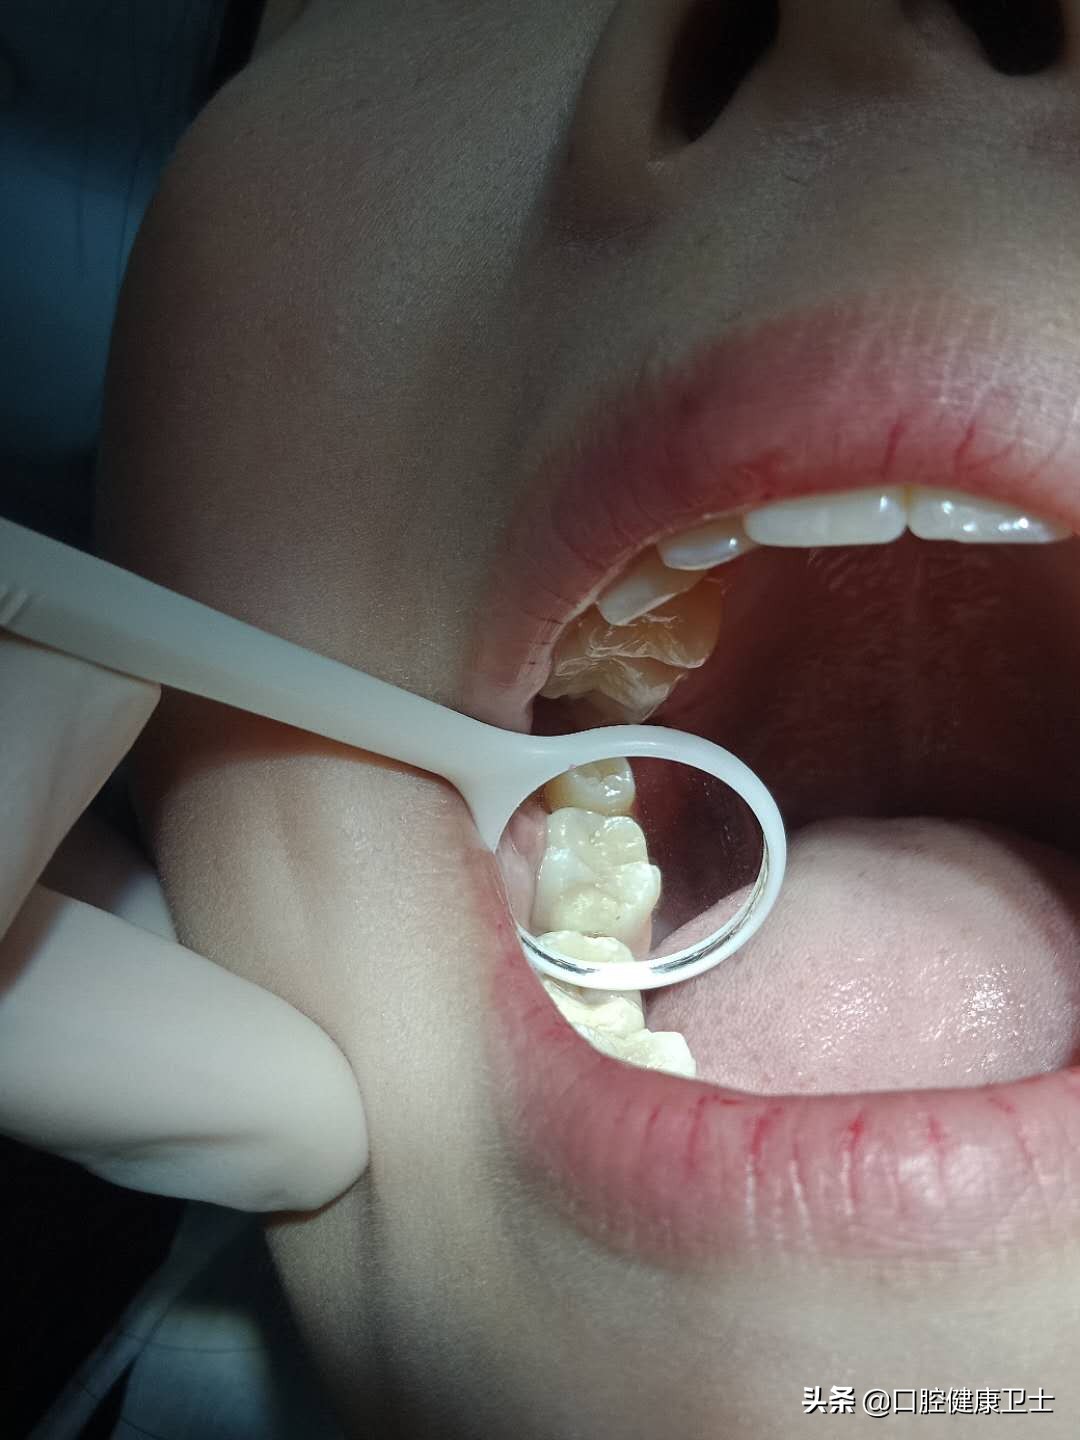

医生:你看,这是你一周前补得牙,现在检查发现了一些问题。

医生:充填体(就是补牙的材料),现在跟正常的牙体组织,不密合,正常的牙齿形态(就是正常的牙齿外形)没有恢复。